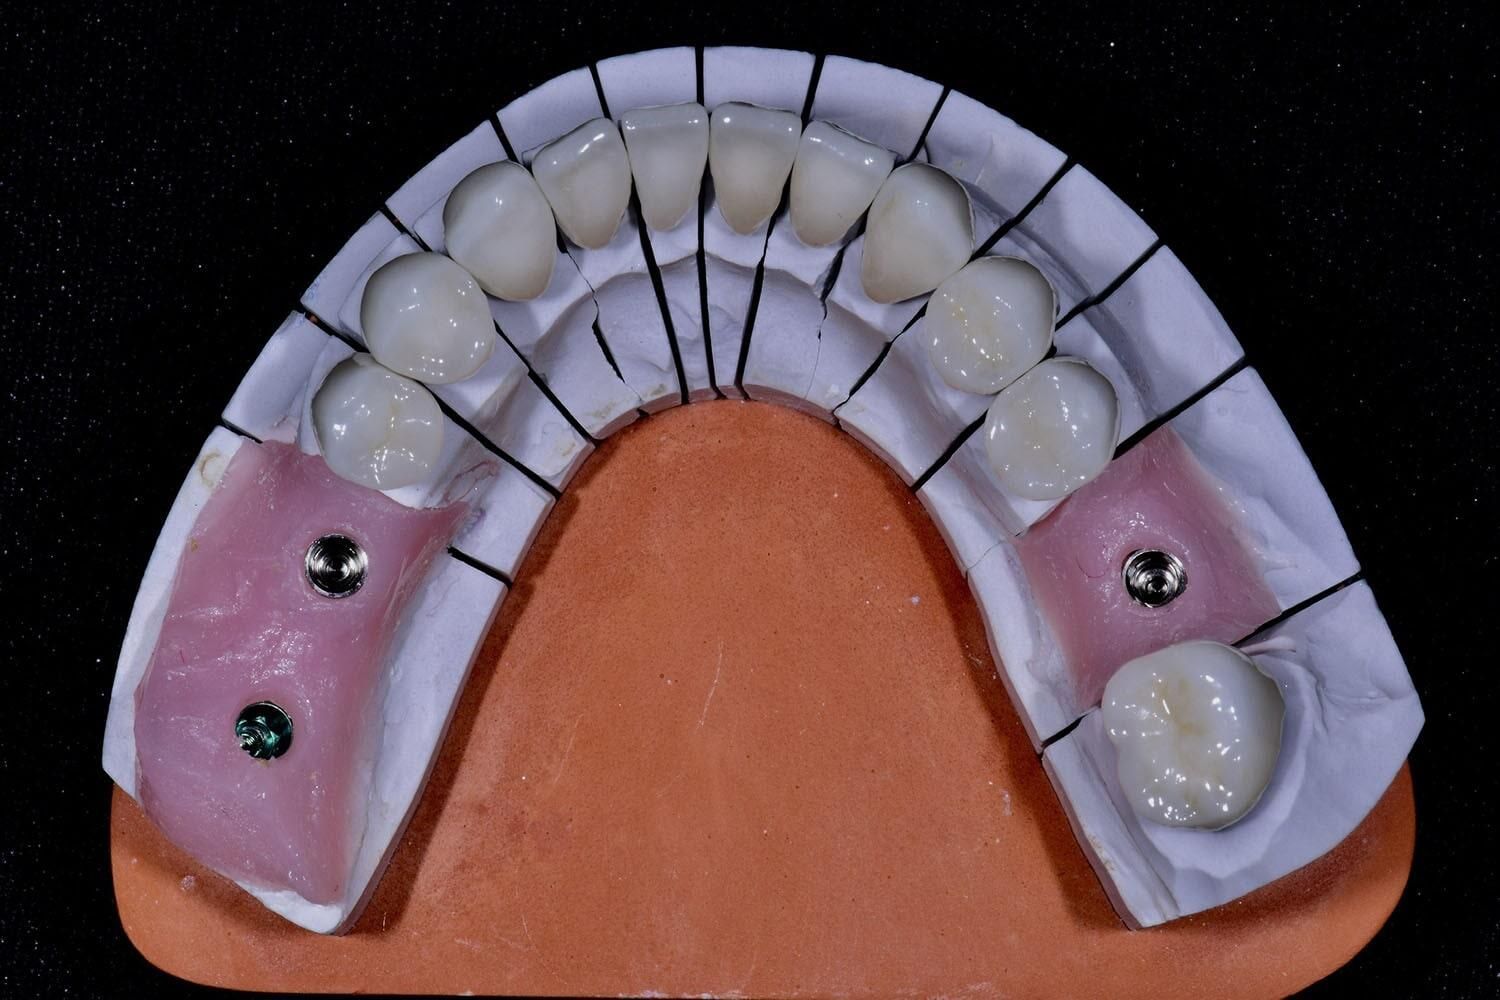

Implantes Dentales

Los implantes dentales son la solución ideal para reemplazar dientes perdidos de manera permanente y segura. Este tratamiento consiste en la colocación de un tornillo de titanio en el hueso maxilar, sobre el cual se fija una corona que imita la apariencia de un diente natural.